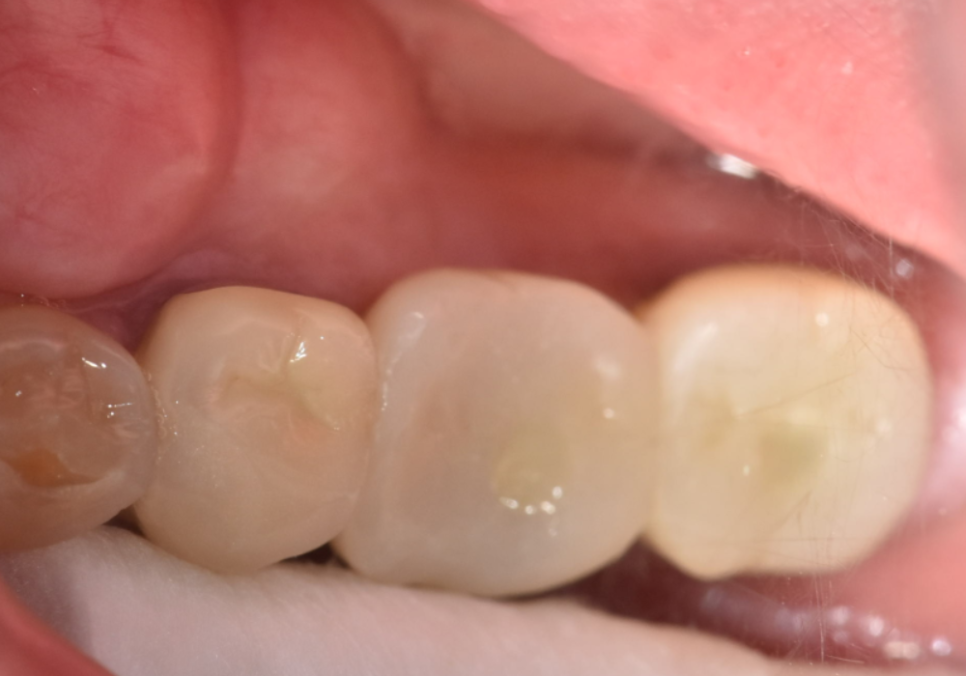

그로부터 약 3개월 후,

임플란트 뿌리와 잇몸뼈가

단단하게 하나로 굳어진 것을 확인한 뒤,

강도와 심미성이 뛰어난 지르코니아 보철물을

올려 치료를 마무리해 드렸습니다. ^^